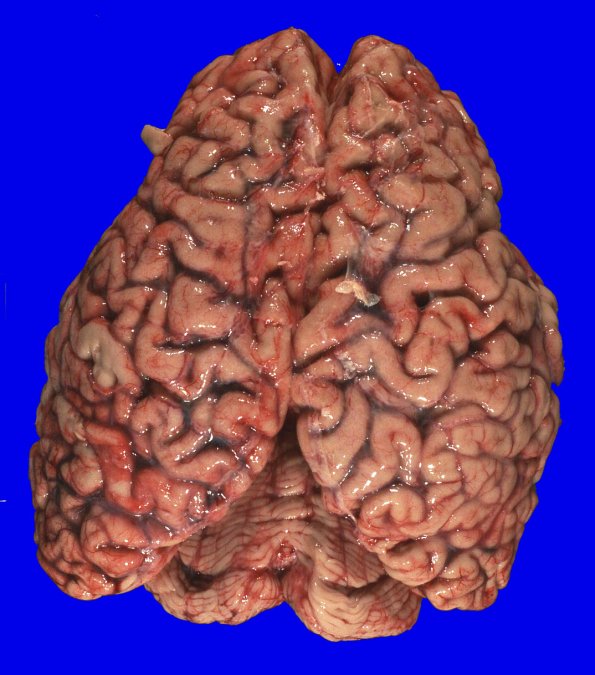

5A1,2 At autopsy the fresh, unfixed brain weighed 1320g. There was mild atrophy of the frontal, temporal, and parietal lobes.